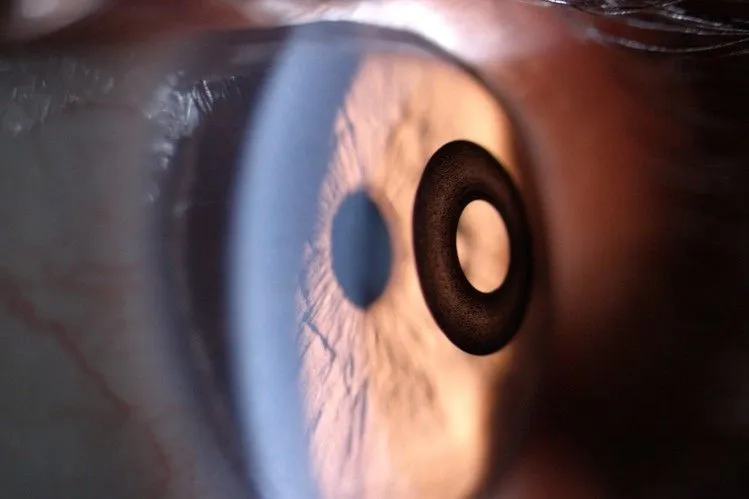

Doughnut-shaped Kamra can replace reading glasses

The Claim: A new doughnut-shaped device from AcuFocus Inc., Irvine, Calif., can dramatically reduce reliance on reading glasses. It’s implanted in the outer layer of just one eye, which will then be used for reading.

The Kamra is a tiny circle of thin black plastic with a hole in the middle. The pinhole “acts a lot like the F stop in a camera,” increasing the range at which a person sees clearly, says Phillip Hoopes Jr. a Draper, Utah, surgeon who has done 80 of the procedures and is a paid consultant to AcuFocus.

The Kamra is nearly imperceptible cosmetically, but at a cocktail party you might notice it in a person with blue eyes, adds Dr. Fox, who has done about 50 of the procedures.